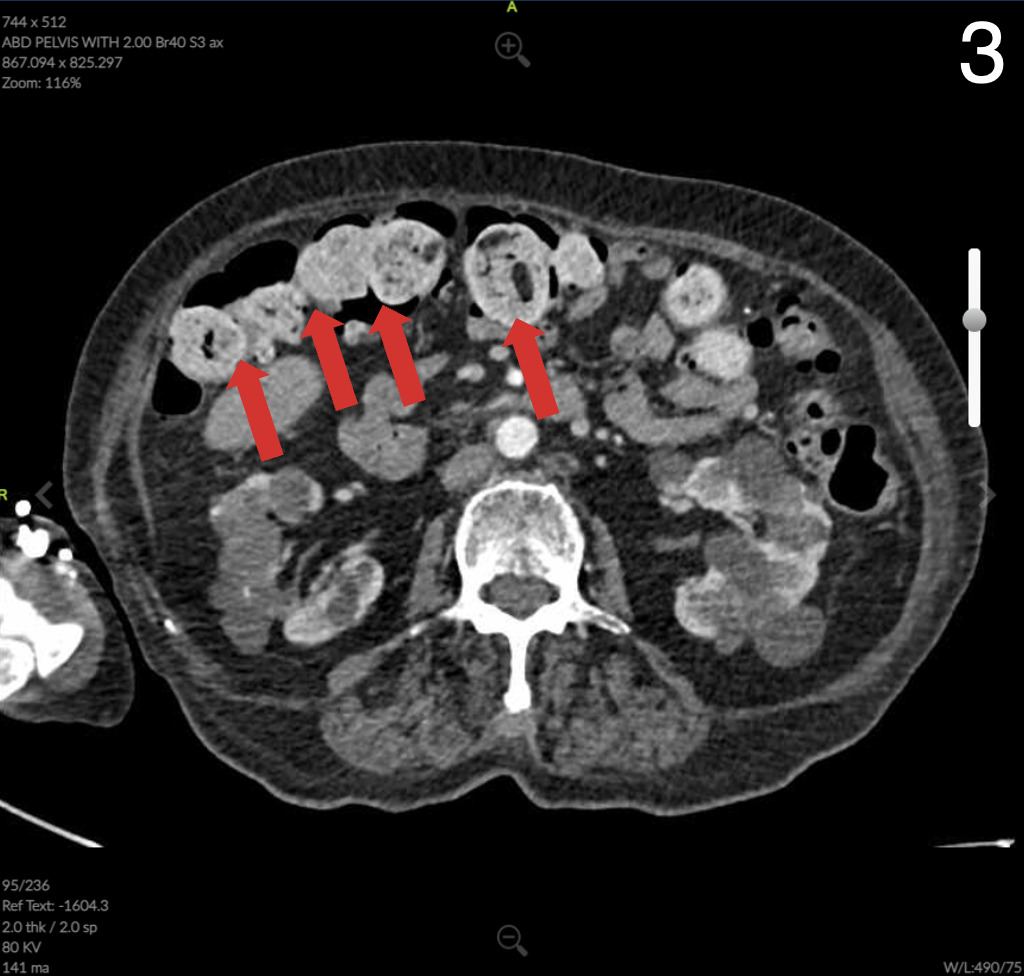

Computed Tomography (CT) of the abdomen and pelvis showed colonic wall thickening particularly in the pelvis close to the vaginal vault. A colonoscopy revealed a severe kink that could not be crossed in the sigmoid colon and extensive diverticular disease.